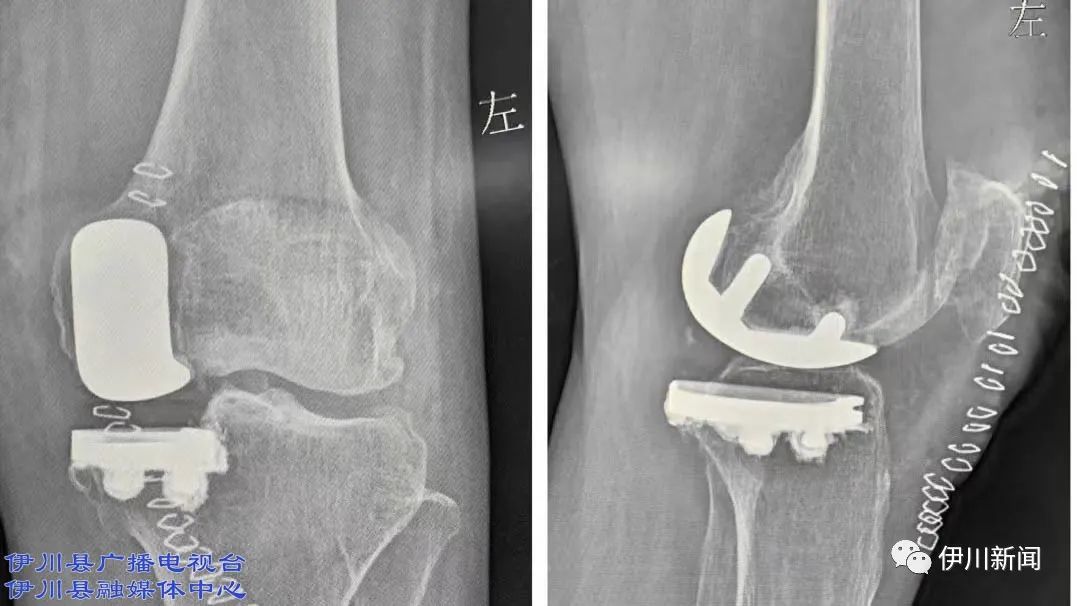

伊川总医院:微创单髁置换!

图片尺寸1077x606